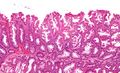

Sessile serrated adenoma 3 very high mag.jpg

صورة مجهرية لورم غدي مشرشر مفلح.

تشخص الأورام الغدية المشرشرة المفلطحة بظهورها المجهري؛ هستولوجياً، تتميز (1) بالتمدد القاعدي للخبايا، (2) تشرشر الخبايا القاعدية، (3) الخبايا الممتدة أفقياً حتى الغشاء القاعدي (الخبايا الأفقية)، و(4) تفرع الخبايا. أكثر الخصائص هذه الخصائص شيوعاً هو التمدد الجانبي للخبايا.

على عكس الأورام الغدية القولونية التقليدية، (مثل الورم الغدي الأنبوبي، الورم الغدي الزغبي)، ليس لديها (عادة) تغيرات نووية (فرط الانصباغ النووي، الاحتشاد النووي، النوية ذات الشكل البيضاوي/شكل السيجار).